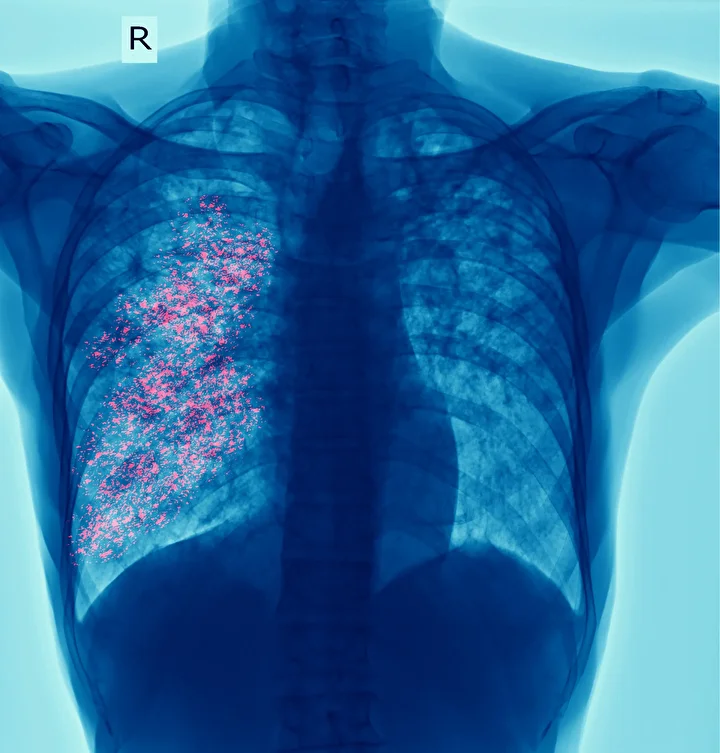

Son 5 yılda vaka sayısında yüzde 10-15 artış gözlendi. Özellikle endüstriyel bölgelerde vaka oranı 3/100 binden 66/100 bine kadar yükseliyor. Sigara, hava kirliliği ve radon gibi çevresel faktörler riski artırıyor. Kadınlarda ise sigara kullanımının artmasıyla vaka sayısı her yıl yüzde 5-7 yükseliyor.

Akciğer kanseri genellikle öksürük, nefes darlığı, göğüs ağrısı ve kilo kaybı ile kendini gösteriyor, ancak erken evrede fark edilmesi güç. 50-80 yaş arası, 20 paket-yıl sigara öyküsü olan bireyler için düşük doz bilgisayarlı tomografi (BT) taraması hayati önem taşıyor. Erken tanı konulan hastalarda sağkalım oranı yüzde 60-90’a kadar çıkabiliyor.